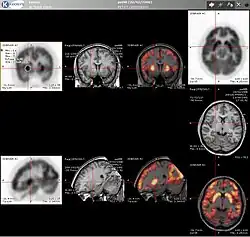

PET scans are increasingly read alongside CT or MRI scans, with the combination (co-registration) giving both anatomic and metabolic information (i.e., what the structure is, and what it is doing biochemically). Because PET imaging is most useful in combination with anatomical imaging, such as CT, modern PET scanners are now available with integrated high-end multi-detector-row CT scanners (PET–CT). Because the two scans can be performed in immediate sequence during the same session, with the patient not changing position between the two types of scans, the two sets of images are more precisely registered, so that areas of abnormality on the PET imaging can be more perfectly correlated with anatomy on the CT images. This is very useful in showing detailed views of moving organs or structures with higher anatomical variation, which is more common outside the brain.